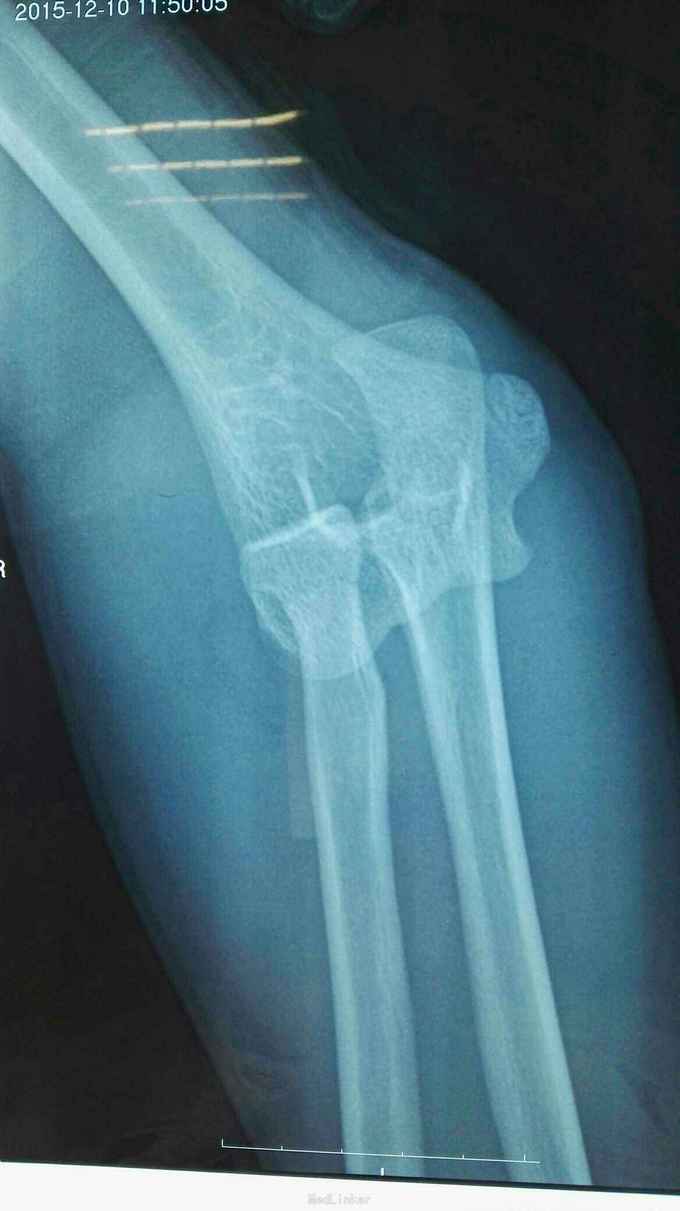

右肘跌伤疼痛伴不能活动1天。 患者,男,14岁,1天前跌倒,感右肘部剧痛,不能活动,急送当地医院拍片示:右肘关节脱位,尺骨冠狀突骨折,右桡骨小头骨折,行手法复位,今来我院就诊。

查体:右肘关节高度肿胀,触痛,活动功能障碍手指末端感觉血运正常。 辅查:x线,CT:右肘关节脱位,右尺骨冠突骨折,右桡骨小头骨折

诊断:右肘恐怖三联症。 治疗:伤后第6天在全麻下行右肘恐怖三联症切开复位内固定术,术中先取肘外侧弧形切口,显露桡骨头,用2枚埋头螺钉固定桡骨头,见右肘外侧副韧带尺侧束断裂,用锚钉固定外侧副韧带。取右肘内侧弧形口,显露冠状突,见冠状突骨折块很小,移位较远,复位,2枚螺钉固定,内侧副韧带前束断裂,修补,术后石膏因定。